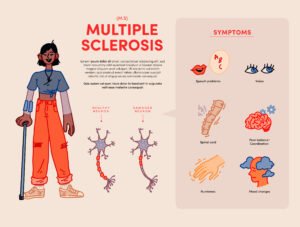

- Multiple Sclerosis